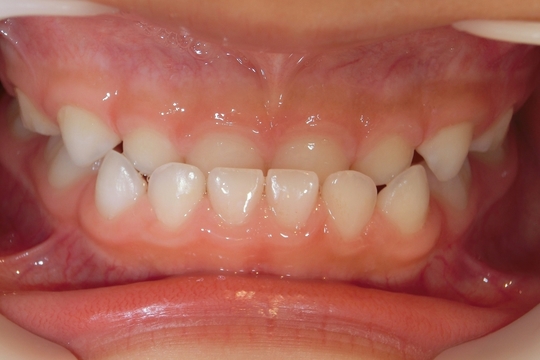

治療前

治療説明 歯科矯正で取り外し可能な矯正方法である床矯正で治療しました

治療期間 2年1か月

治療費200000 円

治療後

治療の副作用(リスク)歯の動き方には個人差があり、予想された治療期間が延長する可能性があります。。床矯正の使用状況、矯正歯科治療には患者さんの協力が必要であり、それらが治療結果や治療期間に影響します。2次矯正が必要になる場合もあります。